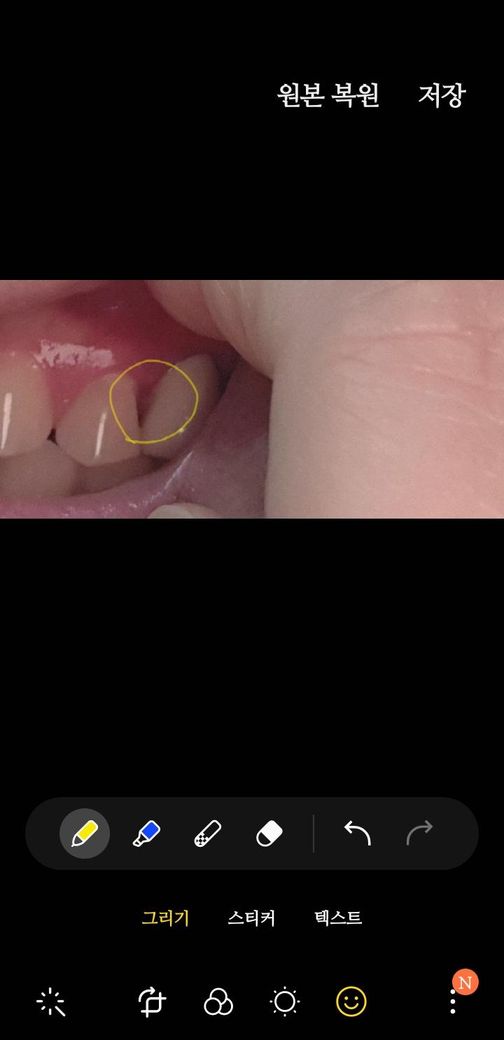

임플란트 보철을 오늘 껴보니 앞니와 공간이 까맣게 많이 생기는데요 제가 앞니가 썪어서 잇몸이 사라져서 저렇다는데요 그럼 보철 모양을 윗부분을 봉긋하게 만들면 되지 않나요? 모양변경이 어렵다고 주장하시는데 답답하네요

• 1번 째 사진